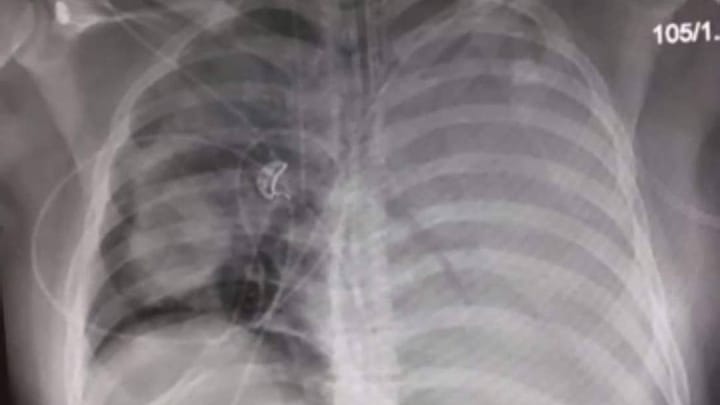

The first image of my lungs, showing the left lung completely filled up and the right one starting to. In xRay terms - White is bad, black is good

- His left lung is full (Dr said it looks like he has a liver in his lung, it's so full). He's operating on half of his right lung. His airway is clear, so that's confusing them too.

- Just got the last xray back and there's a big improvement!

Huge improvement. Lots more black than white and the left lung is coming back to life.